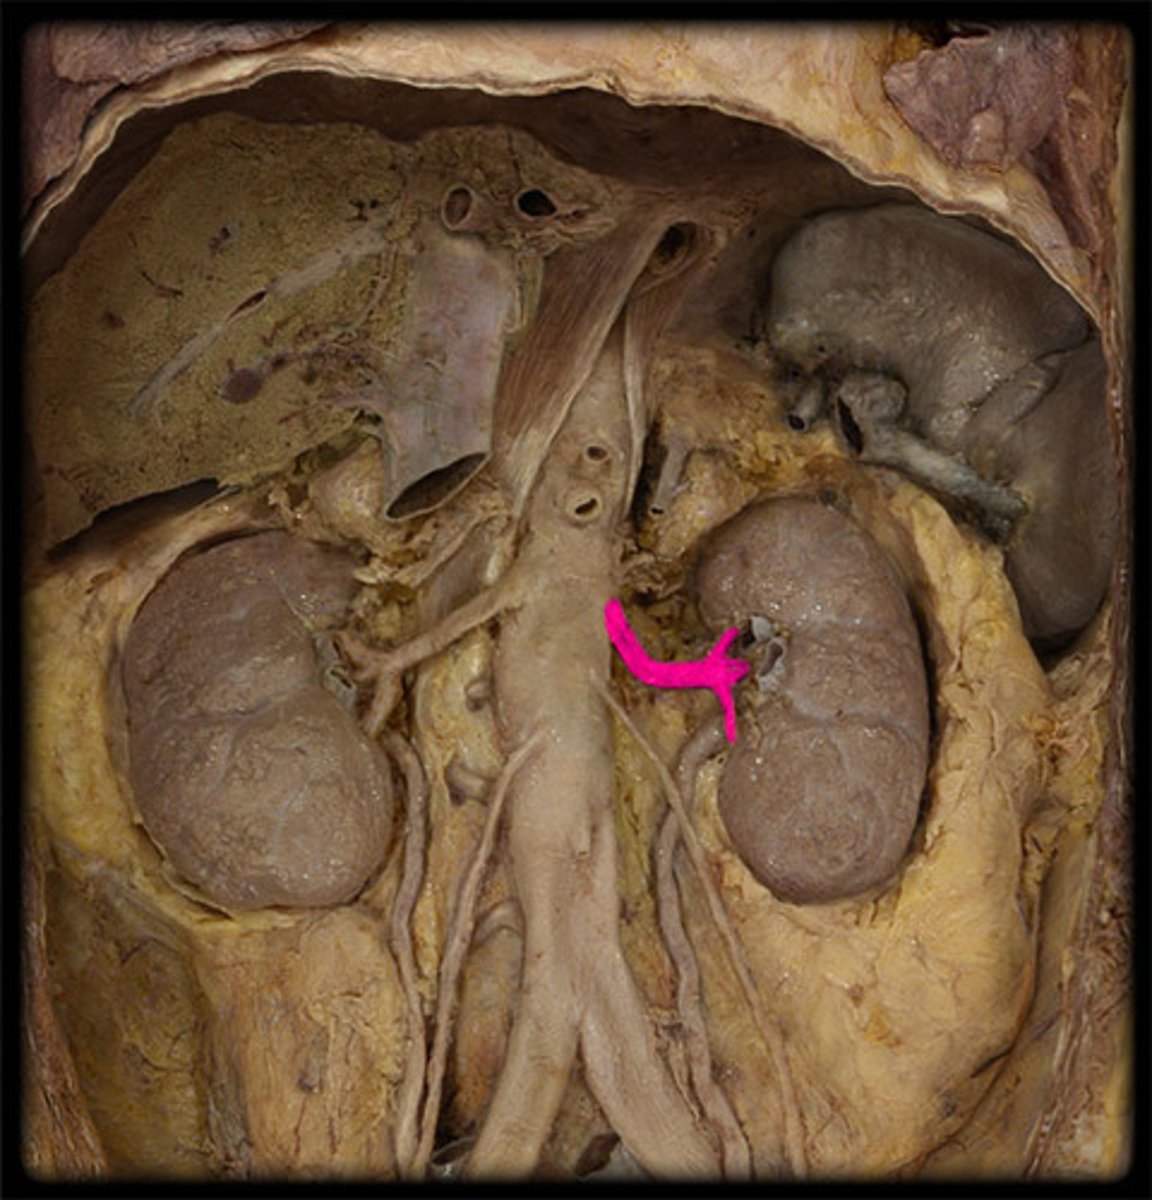

What is this?

Renal vein

Renal artery

Renal pelvis

The celiac trunk branches from the...

Abdominal aorta

What are the branches of the celiac trunk?

Left gastric artery

Splenic artery

Common hepatic artery

What are the splenic artery branches?

Short gastric arteries

Left gastroomental artery